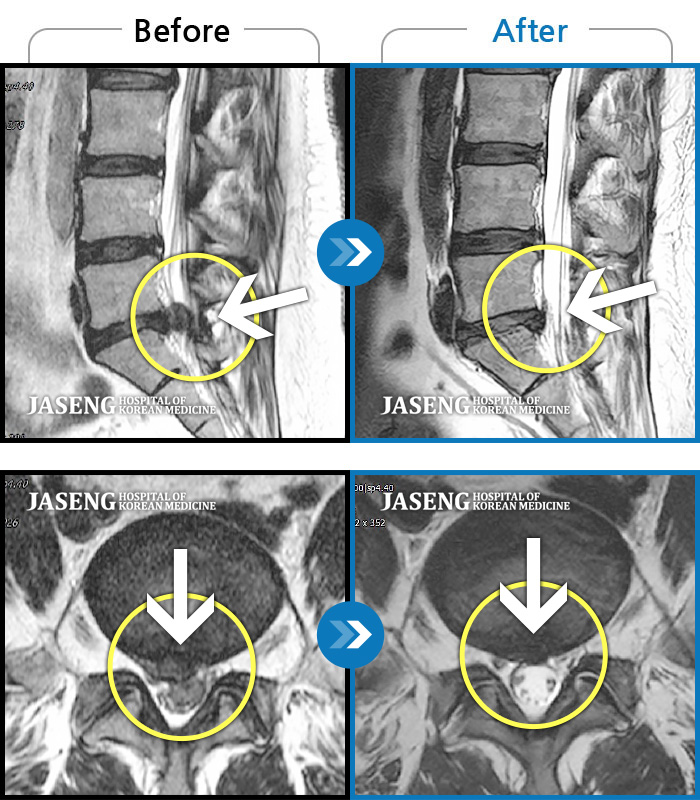

MRI 결과는 추간판협착증 2군데와 추간판탈출되어 터져서 디스크가 좌측으로 흘러내려 좌측 신경을 넓게 누르고 있는 곳이 1군데로 예상보다 심각한 상태였더군요.